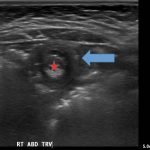

A segment of bowel within the right abdomen that measured approximately 1.6 x 1.5 cm transaxially. It demonstrated a hypoechoic edematous outer loop of bowel (blue arrow) and hyperechoic compressed loop of bowel telescoping within (red star), this is known as the “target sign.”

Intussusception is the invagination or telescoping of part of the intestine into itself. It is the most common cause of intestinal obstruction in children younger than 2 years.1 Ninety-five percent are ileocolic but any part of the small or large intestine can be involved.2 Abdominal pain is the most common symptom.3 Patients classically experience cyclic episodes (10 – 15 minutes) of severe abdominal pain. During these painful episodes, patients are often described as drawing the legs up to the abdomen and screaming in inconsolable pain. Ultrasound is operator dependent, however the sensitivity and specificity for intussusception approaches 100% with an experienced ultrasonographer.4 A good history and physical exam remain important, as the appearance of a “target sign” in the right lower abdomen can also be seen in appendicitis, caused by an appendixwith an appendicolith.